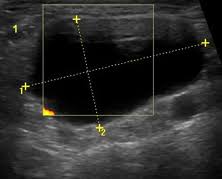

What Does Neck Cancer Look Like On An Ultrasound : Neck Lumps Differential Diagnosis Investigation Teachmesurgery : In the framework of such terms as ultrasound of the neck, can be performed the following studies:. Ultrasound is used to see the thyroid gland and the lymph node of the neck. Fna is generally done on all thyroid nodules that are big enough to be felt. A neck lump or nodule is the most common symptom of thyroid cancer. A lump will form when a cancer cell infiltrates the capsule and multiplies. A nodule or a growth in the thyroid can be seen and identified.

Enlarged Lymph Nodes In Head And Neck Cancer Analysis With Triplex Ultrasonography Sathyanarayan V Siva Bharani K Ann Maxillofac Surg from www.amsjournal.com Ultrasound an ultrasound is sometimes used, especially to look at the thyroid, salivary glands and lymph glands in the neck. Ultrasonography of neck lymph nodes; As thyroid cancer gets more advanced, you might notice symptoms like: Lumps can also form in the lips. A small lump on the neck usually is a lymph node, a small sebaceous cyst or a lipoma, although it could be something else. Reactive lymph nodes look different on ultrasound to lymphoma, so i'm sure the report to the gp will be the same as what she told you. Ultrasound is used to see the thyroid gland and the lymph node of the neck. During biopsy, the ultrasound helps make sure they are getting fna samples from the right areas.

The sonographer stands facing the ultrasound and uses their right hand to move the transducer on the patient's neck, thus simultaneously facing both the ultrasound monitor ( on the left) and the patient's face ( on the right) figure 4.5. Are there signs of thyroid cancer on ultrasound? Sounds like they've been enlarged from an infection, maybe fighting one you weren't even aware of. A neck lump or nodule is the most common symptom of thyroid cancer. How a nodule looks on ultrasound can sometimes suggest if it is likely to be a cancer, but ultrasound can't tell for sure. Physical examination/blood and urine tests. Skin cancer is by far the most common type of cancer. An ultrasound of the neck is used to examine the carotid arteries located on each side of a patient's neck. The doctor will also inspect the nose, mouth, throat, and tongue for abnormalities, often using a light and a mirror for a. During a physical examination, the doctor feels for any lumps on the neck, lips, gums, and cheeks. Unfortunately cancer of the thyroid will not show up on an ultrasound. Most of the time, patients in the low risk group are simply monitored by ultrasound. An ultrasound scanner uses high frequency sound waves to create images of the internal soft tissues of the face and neck.

Non Thyroid Cystic Masses Identified On Neck Ultrasound from www.healio.com If you have a lump on it. During a physical examination, the doctor feels for any lumps on the neck, lips, gums, and cheeks. Air and bone also reflect sound waves. This means that they are larger than about 1 centimeter (about 1/2 inch) across. A neck ultrasound can be used to observe the thyroid gland to look for nodules, growths, or tumors. Epidemiology it typically presents in younger women with an average age of onset at around 45 y. Ultrasounds are usually quick and most don't require special preparation. The sonographer stands facing the ultrasound and uses their right hand to move the transducer on the patient's neck, thus simultaneously facing both the ultrasound monitor ( on the left) and the patient's face ( on the right) figure 4.5.

Doctors often use them to guide a needle during a biopsy. Carotid ultrasound tests for blocked or narrowed carotid arteries, which can increase the. If left unchecked, the cancer can break out of the lymph node and spread to the surrounding. This picture gallery contains some examples of the more common. Ultrasound is relatively quick and simple test that gives very useful information about the soft tissues in the head and neck region including the lymph. Thyroid nodules, or lumps, are very common.most aren't cancer. Reactive lymph nodes look different on ultrasound to lymphoma, so i'm sure the report to the gp will be the same as what she told you. Trusted, accurate neck ultrasound, from the experts in anchorage. The doctor will also inspect the nose, mouth, throat, and tongue for abnormalities, often using a light and a mirror for a. Epidemiology it typically presents in younger women with an average age of onset at around 45 y. Malignant cyst look more complex and may have solid areas. Doctors in 147 specialties are here to answer your questions or offer you advice, prescriptions, and more. Two in three cases of thyroid cancer occur in people under age 55, and 75%.